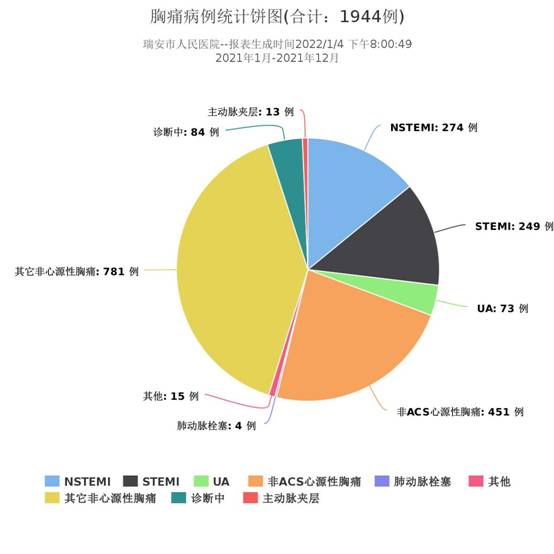

在过去的2021年中,瑞安市胸痛中心获得了长足的进步及不菲的成绩。首先,2021年本中心共收治急诊胸痛患者达1944例,包括了急性ST段抬高型心肌梗死患者249例,非ST段抬高型心肌梗死患者274例,不稳定型心绞痛患者73例,还包括了13例的主动脉夹层患者及4例的肺栓塞患者,经受住了临床工作的极大考验。2021年心内科共开展冠脉介入手术1217例,较20年的911例增长了33.6%,在新冠疫情的影响下,仍能取得这样的成绩实属不易。除了手术量上面的增长,手术的复杂程度也大大增加,血管内超声(IVUS)、血流储备分数测定(FFR)等功能学检查也广泛开展,让手术的精准化、标准化进一步得到提升。